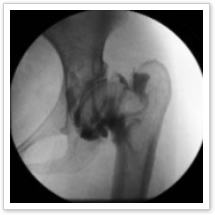

当クリニックでは、整形外科領域を中心とした診断と治療の可能性を拡大する目的で、一般撮影機能に、透視機能を搭載した最新型X線撮影装置(レントゲン装置)を導入しました。

※透視機能とは、レントゲンを連続撮影し、即座に画像を表示させる機能です。

当クリニックの導入したX線撮影装置は、島津製作所製RADIOTEX FLUORO IIです。

島津製作所製RADIOTEX FLUORO IIは、リアルタイムに骨の観察が行えますので、単純に骨の動きを観察するだけでなく、部位を確認しながらの麻酔治療や整復術を行うことができます。

更に、緊急時の患部確認・異物の確認や不安定な関節に動的負荷をかけたときの診断にも、より迅速且つ的確に行うことが可能になります。